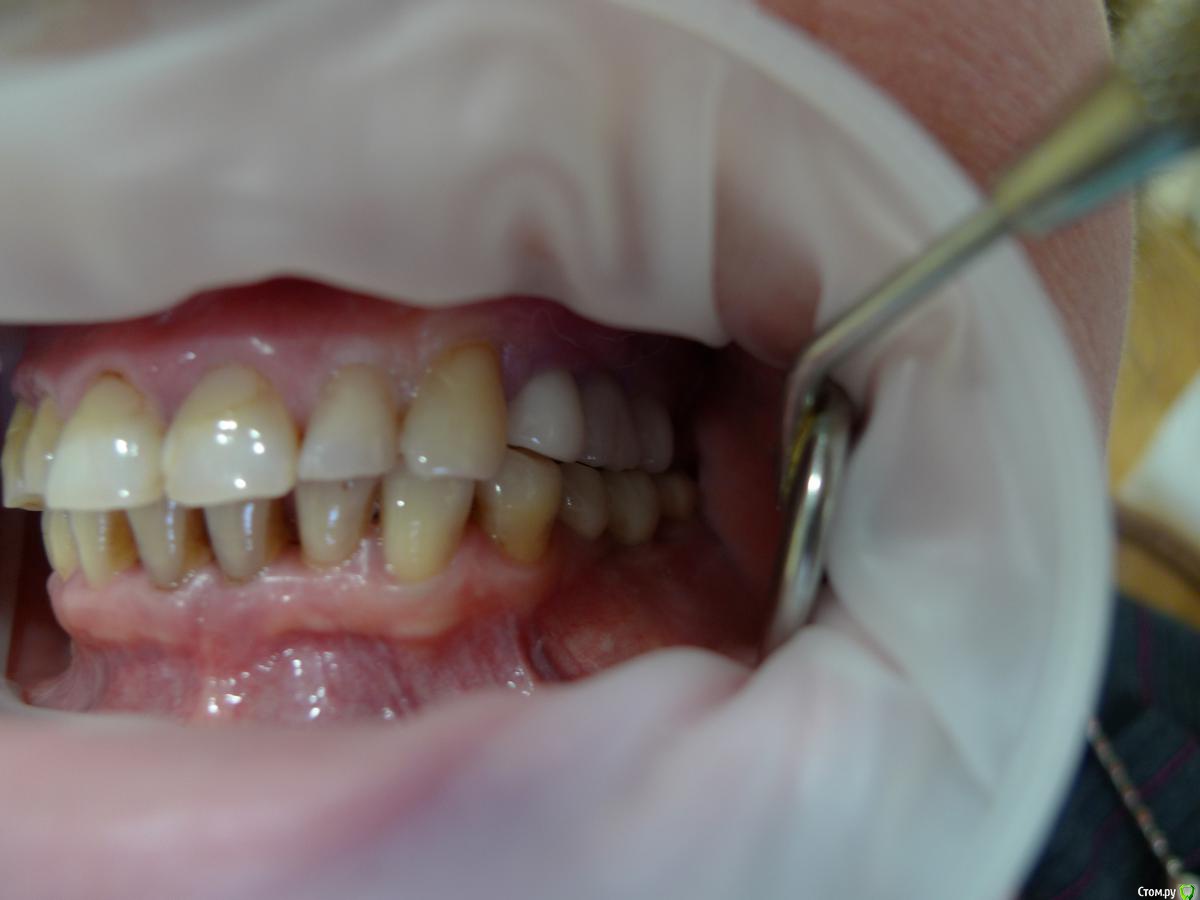

alekszander Опубликовано 26 февраля, 2016 Автор Поделиться Опубликовано 26 февраля, 2016 Прилагаю фото в полости рта (прошу прощения фото на мыльницу Leica) - ретракторов и зеркал пока нет. Ссылка на комментарий

Евгений Ходыкин Опубликовано 26 февраля, 2016 Поделиться Опубликовано 26 февраля, 2016 Ты чот видишь по фоткам этим? Ссылка на комментарий

alekszander Опубликовано 26 февраля, 2016 Автор Поделиться Опубликовано 26 февраля, 2016 Ты чот видишь по фоткам этим? согласен - фотки гумно. Но какие получились, не зеркалка же(хотя привык на нее фотать но в другой клинике) Ссылка на комментарий